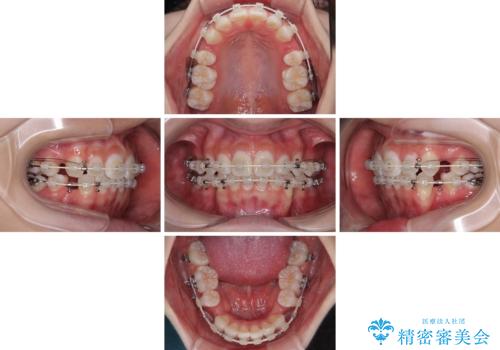

- 矯正装置

- 審美装置

- 治療期間

- 2年

- 治療回数

- 10-30回